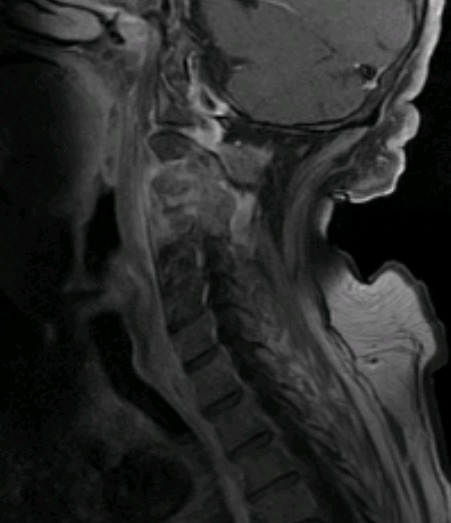

La resonancia postoperatoria demostró una adecuada descompresión. El paciente fue derivado para tto oncológico de rescate. La evolución postoperatoria fue favorable desde el punto de vista neurológico, con recuperación progresiva de la focalidad hasta autonomía completa.

RM 6 meses postor